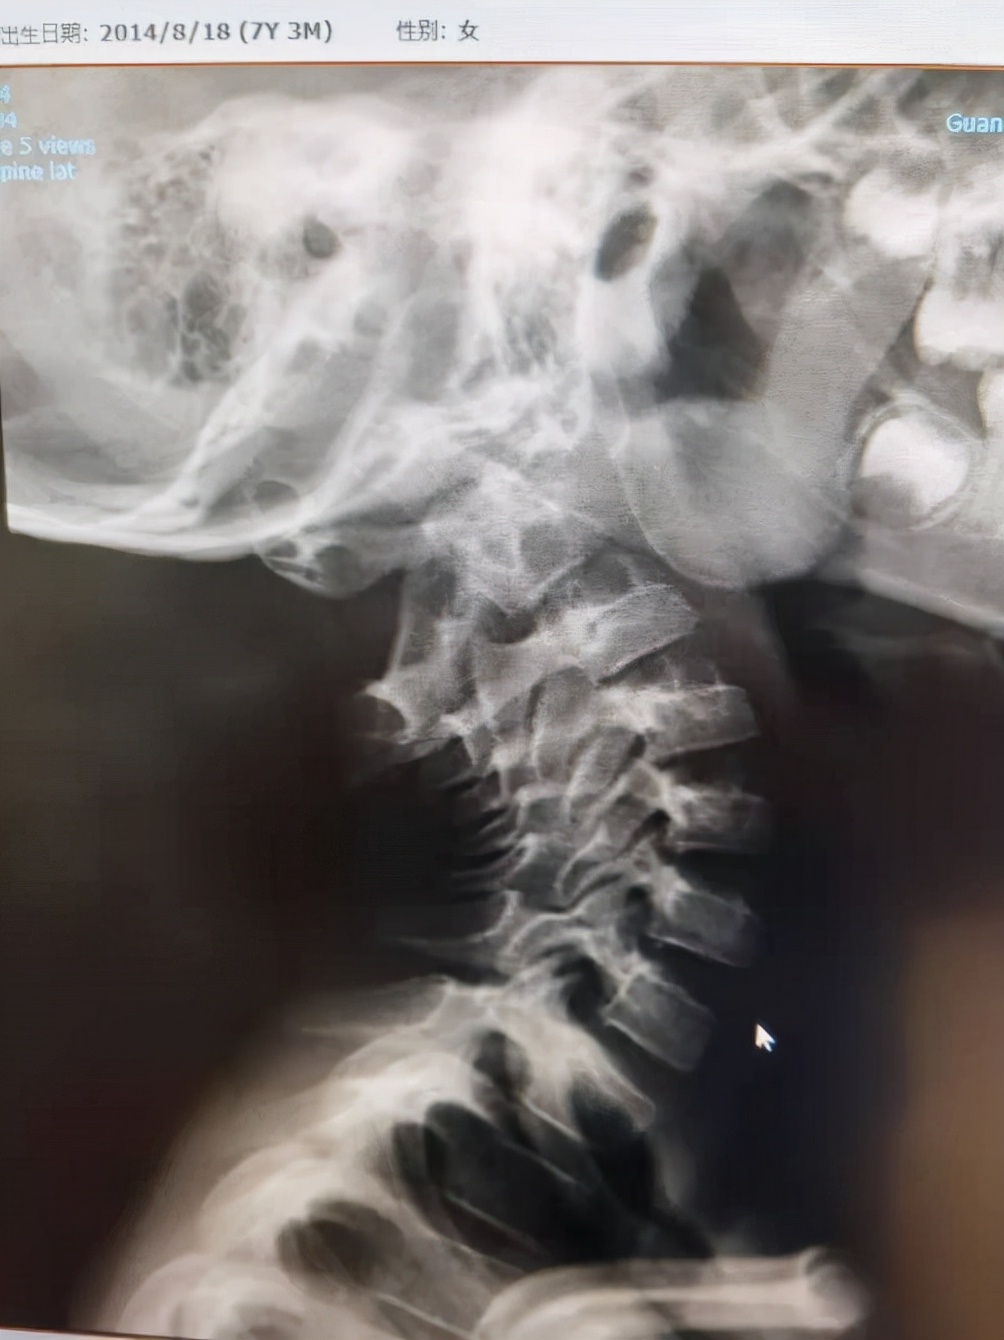

这位我们最近治疗的一例患儿,七岁女孩,头颈倾斜不能转动半年。小女孩非常可爱活泼,可惜头颈倾斜影响了她的活动和学习。

检查显示严重的寰枢椎固定脱位,脊髓也受到压迫。